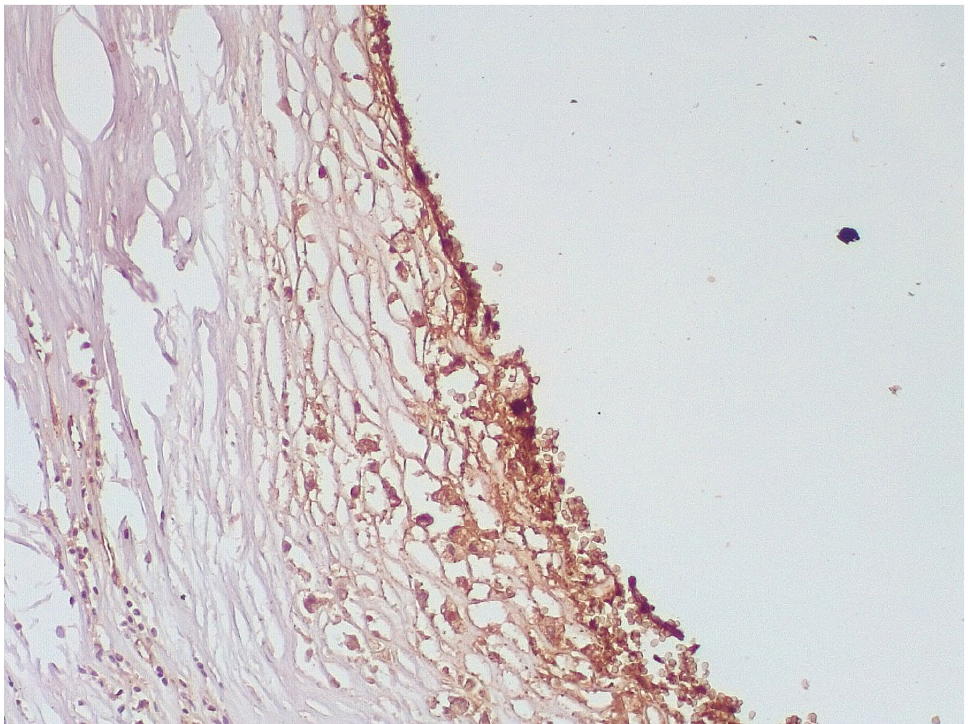

Обращало внимание, что в местах «оголенного» эндотелия КА отмечалась слабая экспрессия белка CD31, что указывало на выраженные дистрофические и некробиотические изменения клеток (рис. 2). При этом экспрессия ФВ была яркой, выраженной на всем протяжении интимы КА (рис. 3).

Сохранялась резковыраженная яркая экспрессия ФВ как со стороны интимы, так и субинтимально, в участках альтерации атером (рис. 8). В то же время экспрессия белка CD31 была негативной на всем протяжении стенок КА.